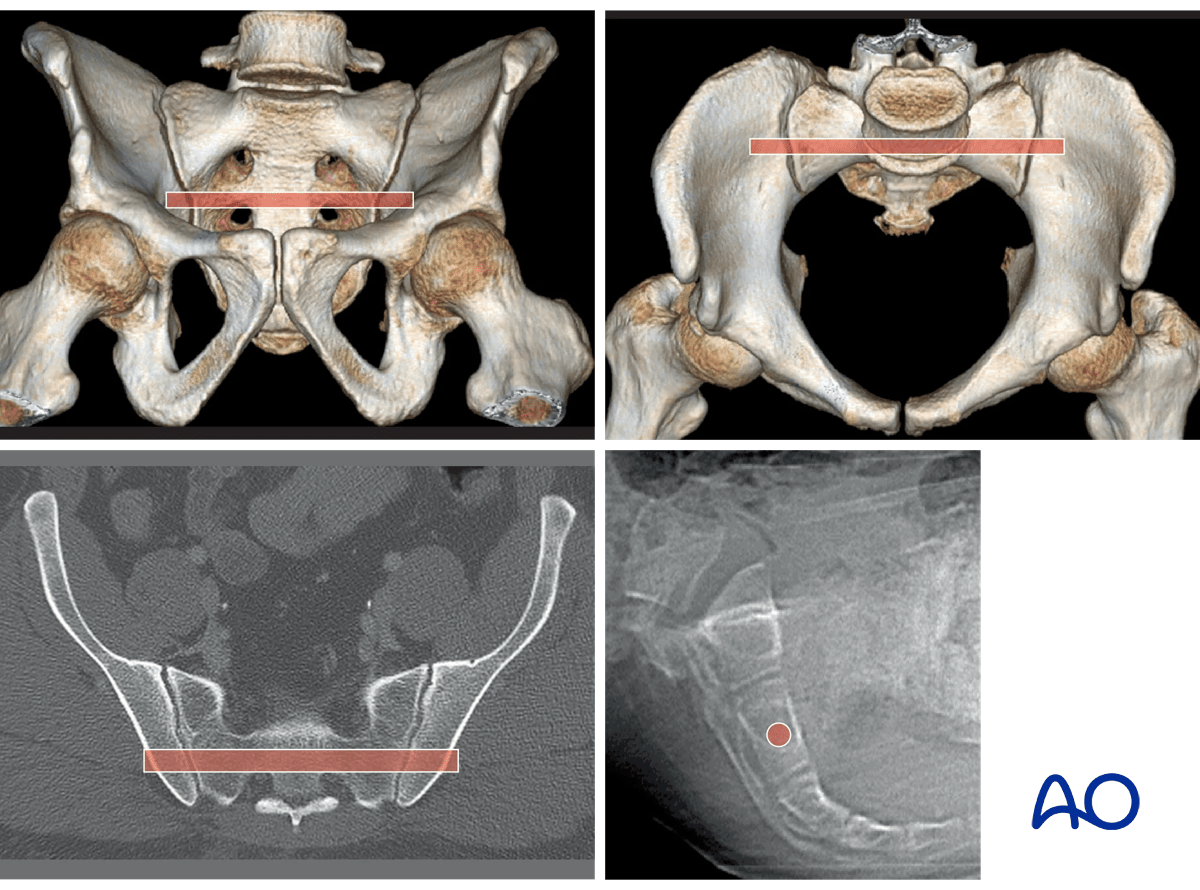

Variable in utero segmentation of the lumbo-sacral somites produces abnormal (“dysmorphic”) upper sacral anatomy in approximately one-third of patients. These variations must be recognized because they compromise normally safe intraosseous pathways for ISS.

The upper images show a normal pelvis; the lower ones are of a dysmorphic pelvis.

Notice, on the 3D CTs, the differences in sacral alar anatomy, with corresponding upper sacral segment deficiencies on the dysmorphic axial CT view.

In such cases, the second sacral level may be better for an iliosacral screw

Sacral deformities may be unilateral or bilateral. Bilateral dysmorphism may be symmetrical, or not.

This case shows an individual with symmetrical upper sacral dysmorphism.

The lumbosacral disc is near the level of the iliac crests, not below them as is normal. There is a residual disc between the upper and second sacral segments. The uppermost anterior sacral foramina are not round, as the lower ones are. The superior alar slope is steeper, from medial to lateral, and from posterior to anterior.

The upper sacral alar anterior cortical limit appears as an indentation (white arrows) relative to the alar anterior cortical of the second sacral segment (yellow arrows). The upper and second sacral alar anterior cortical limits are different but easily seen on the inlet view. The surgeon must understand these differences and then visualize them under image intensifier in the operating room because iliosacral screws must remain posterior to these alar cortical limits.